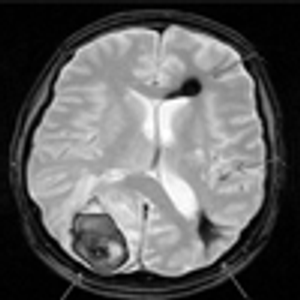

A 59-year-old woman with chronic hepatitis C presented with abdominal pain that had grown progressively worse during the past 3 months.